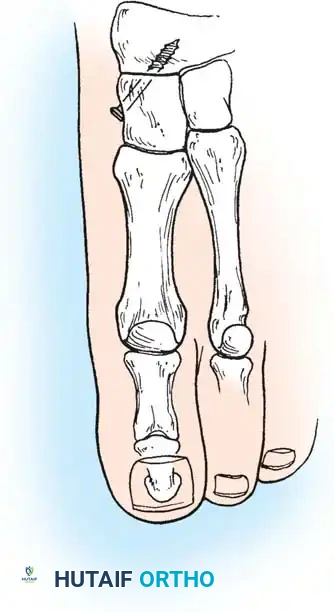

4. Plantar Flexion Osteotomy of the Medial Cuneiform (Cotton Procedure)

Following hindfoot correction (via calcaneal osteotomy), the forefoot may remain in fixed supination (forefoot varus). The Cotton osteotomy plantarflexes the first ray to restore a plantigrade tripod foot.

* Approach: Make a dorsal longitudinal incision over the medial cuneiform. Protect the medial branch of the superficial peroneal nerve and the extensor hallucis longus tendon.

* Osteotomy: Perform a dorsal opening-wedge osteotomy of the medial cuneiform using a sagittal saw. Leave the plantar cortex intact to act as a hinge.

* Correction: Open the osteotomy dorsally with an osteotome until the first metatarsal head is brought down to the level of the lesser metatarsals (plantigrade).

- Grafting and Fixation: Insert a structural wedge graft (autograft or allograft) into the dorsal defect. Fixation is achieved with a dorsal spanning plate or staples.